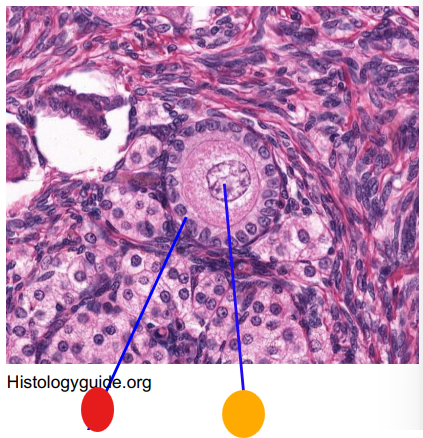

red

granulosa cells

orange

primary oocyte

what is this

primary follicle